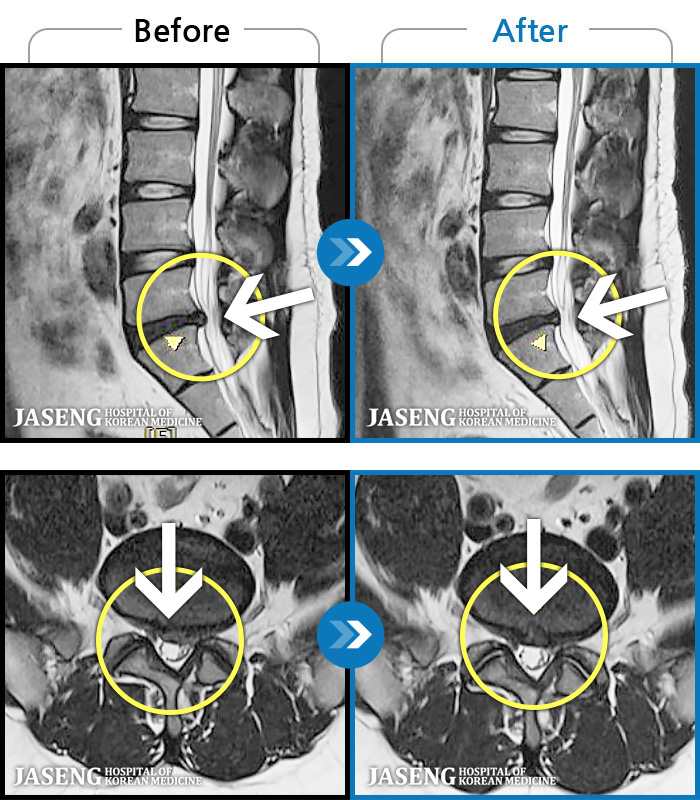

- MRI ġ

MRI ġ

96 MRI ũ ʸ Ȯϼ.